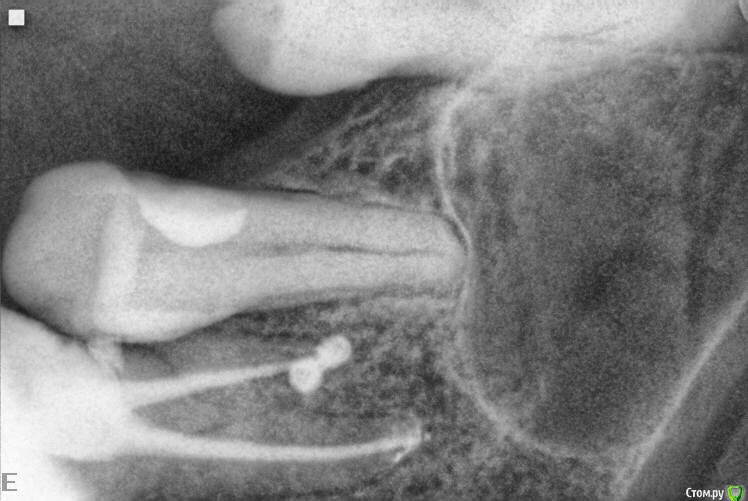

Fred Опубликовано 11 сентября, 2015 Поделиться Опубликовано 11 сентября, 2015 По-моему - это идеальный вариант, когда в канал мастерштифтом равномерно нагнетен силер, и в апексе канала - только он. Почему? А потому, что это моноблок, нет стыков силер-гутта. Вот мой сегодняшний случай. Специально я так не делал, но лезть за ступень каким-н финишным файлом я побоялся. Поэтому гидравлика сделала свое. http://s3.postimg.org/idgioqv0j/Untitled_2.jpg Ссылка на комментарий

Fred Опубликовано 25 сентября, 2015 Автор Поделиться Опубликовано 25 сентября, 2015 Вот моя теория, почему так даже лучше. http://s17.postimg.org/tmdfxnngv/Untitled_5.jpg Ссылка на комментарий